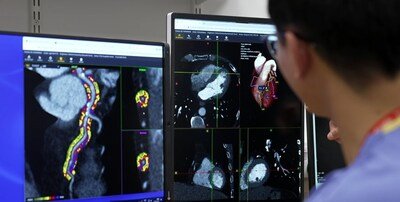

Philips expands commercial availability real-time AI-enabled light-based 3D navigation solution for image-guided therapy

Real-time AI-enabled 3D device visualisation powered by light instead of X-ray, improving navigation in complex endovascular procedures...